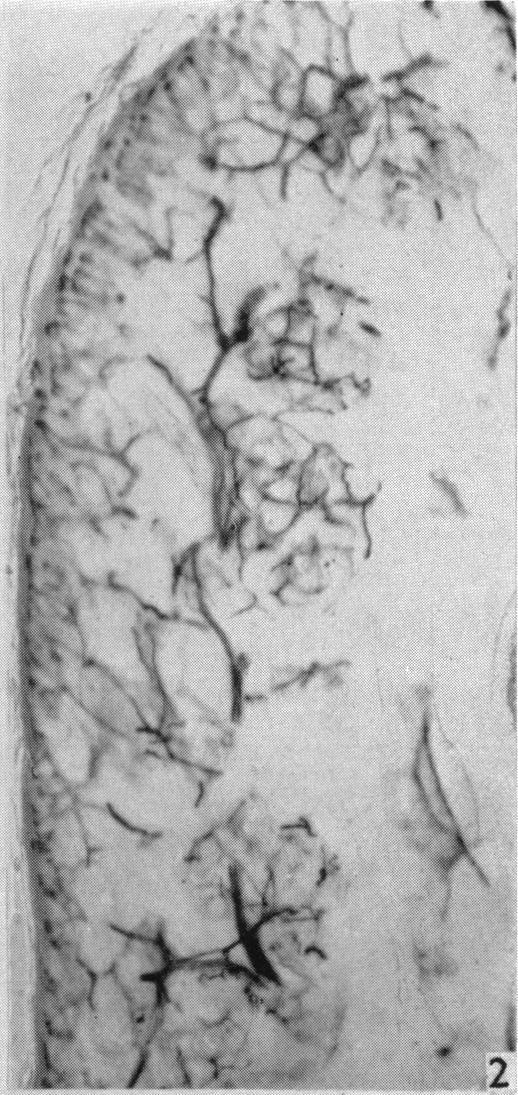

BECKETT E B, BOURNE G H, MONTAGNA W

J Physiol. 1956 Oct 29;134(1):202-6. doi: 10.1113/jphysiol.1956.sp005636.